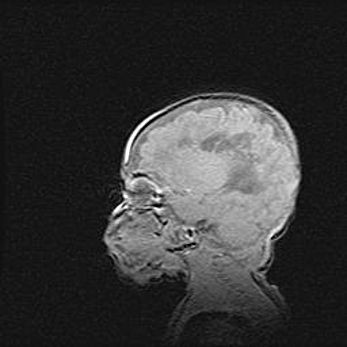

Неполная лизэнцефалия (пахигирия). Открытая гидроцефалия.

Возраст: 17 дней

Вес: 3110 г

Пол: мужской

Окружность головы: 33,5 см

Срок гестации: 35-36 недель

Лизэнцефалия—недоразвитие корковой пластинки и мозговых извилин в результате нарушения миграции нейронов коры. Поверхность мозговых полушарий гладкая. Микроскопически выявляется отсутствие нормальных слоев коры и скопление групп нейронов в подкорковом белом веществе.

Пахигирия—уменьшение числа вторичных извилин. В пораженном полушарии нервные клетки образуют толстый недифференцированный слой с неправильно расположенными нервными волокнами и группами гетеротопных клеток. Нервные клетки незрелые. Белое вещество истончено. При этом нередко аномально развит корково-спинномозговой путь.